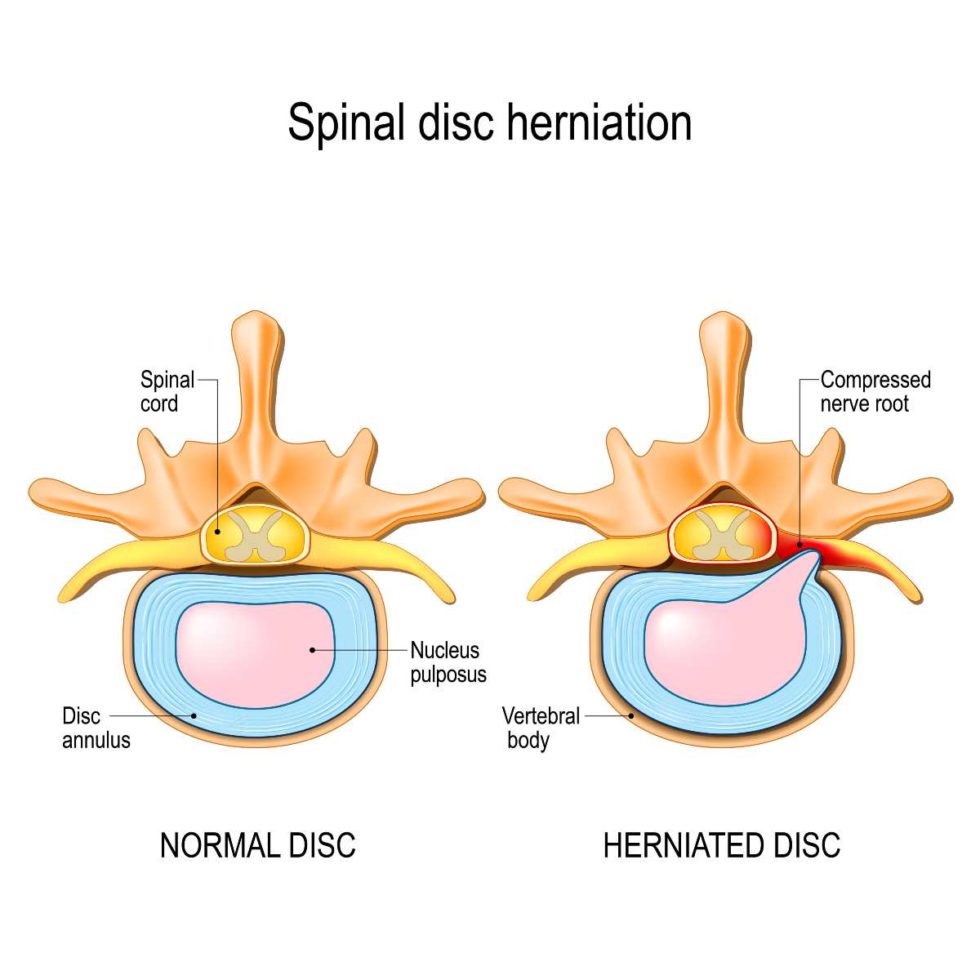

What is the difference between a bulging disc and a herniated disc?

Bulging and Herniated Discs – Explained | Physical Health Care